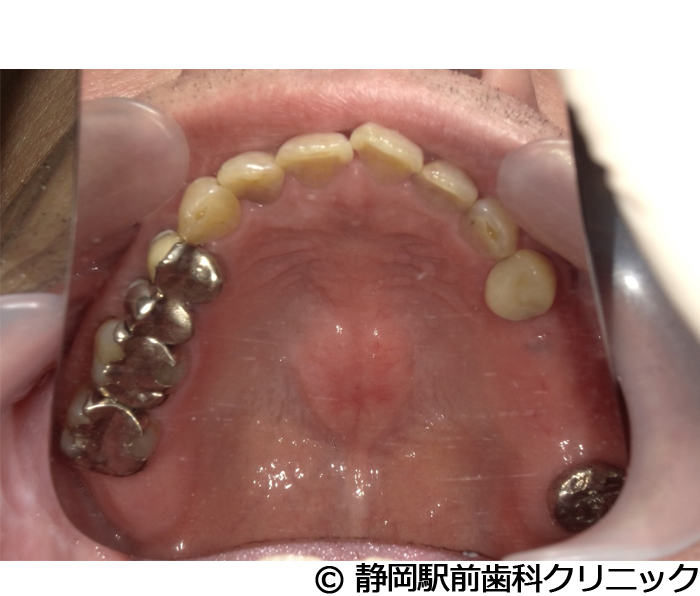

【症例5】全顎的インプラントとセラミックによる審美補綴

- 治療前

- 治療後

- 治療名

- 全顎的インプラントとセラミックによる審美補綴

- 費用

- 1,800,000円(税込)

- 期間

- 1年6ヵ月

治療内容

患者様の症状

-

全体的に歯がないため、噛めない。インプラント治療希望。

治療方法

全体的に残根は抜歯を行い、術前にCTを撮影し緻密に治療計画を立てた。インプラント埋入はブロックごとに行い、噛み合わせの調整を重ねた後、人工歯を被せて咬合と審美の回復を行いました。

治療結果

しっかり奥歯で食べ物を噛み切ることができるようになり、何でも食べることができるようになったと喜んでいただくことができました。口元を気にせずに笑うこともできるようになり、見た目もキレイになったとご満足いただけました。

※治療結果は個人差があります。

治療を行う上での注意点(リスク・副作用)

術後は、出血、腫れ、痛みなどが出る可能性があります。